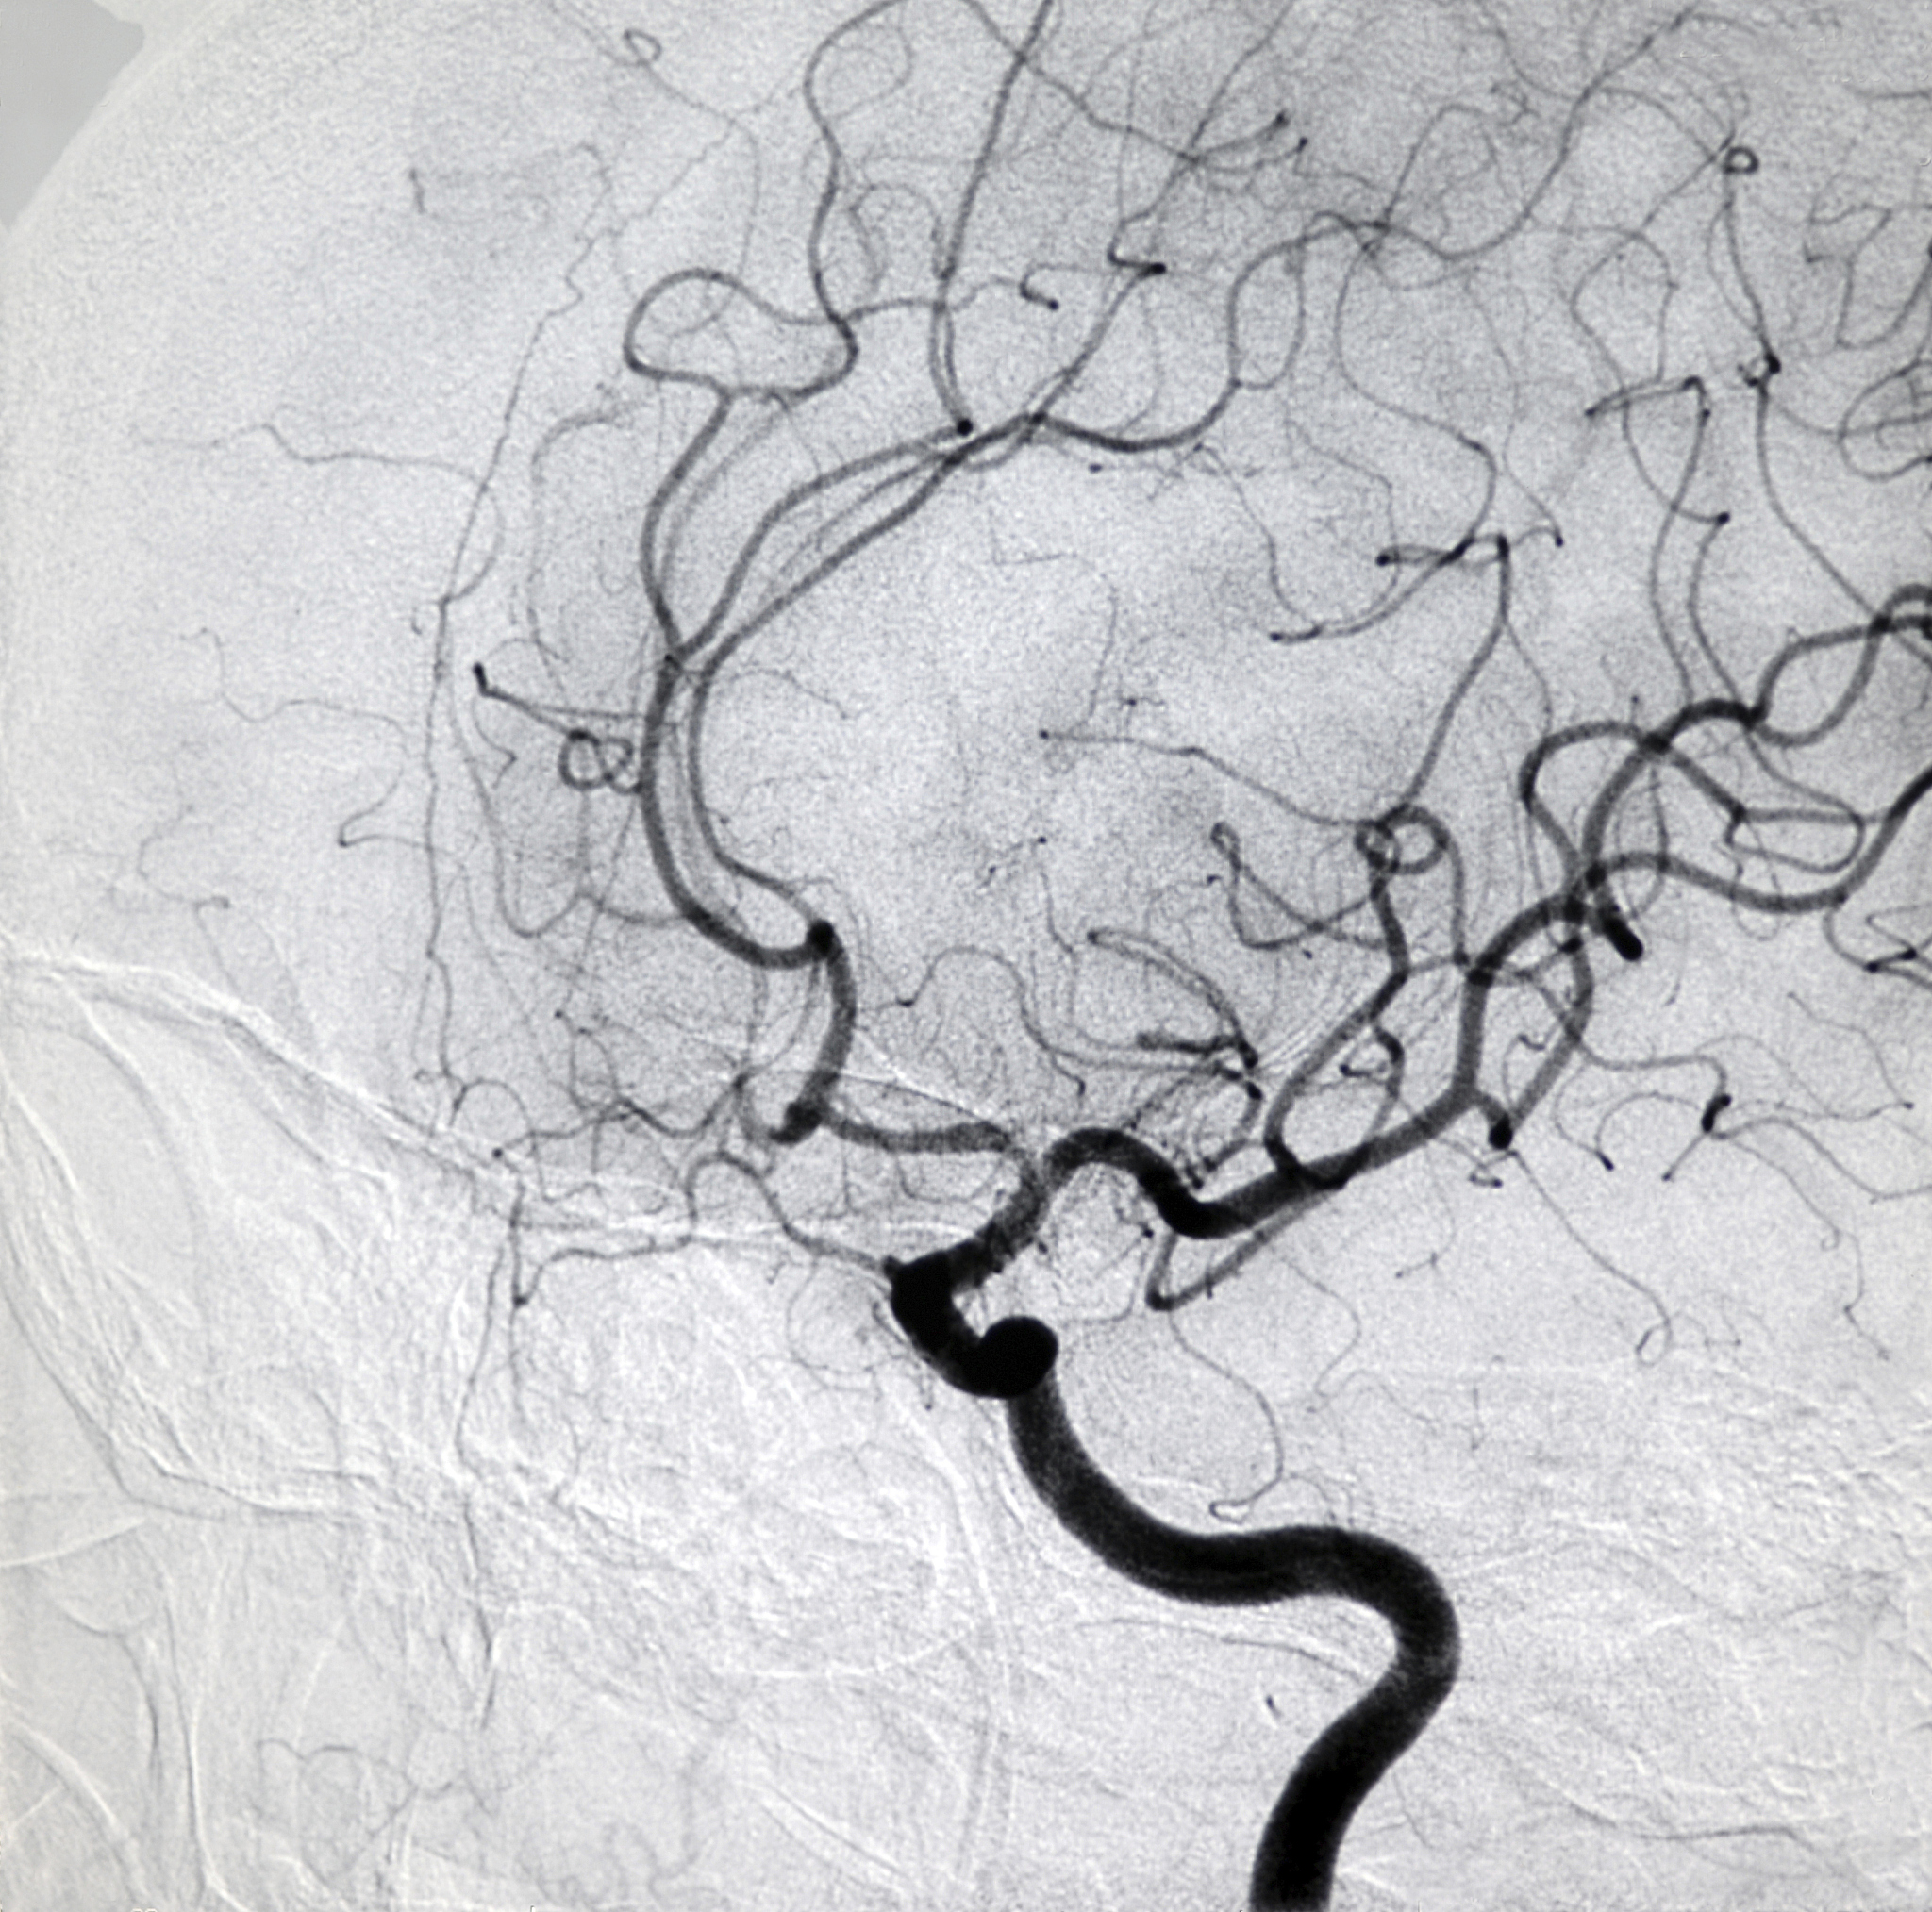

In summary, the diagnosis of ultrasound contrast examination is a ruptured vulnerable plaque with ulcer formation in the right carotid artery, accompanied by the formation of a free-floating thrombus, and moderate stenosis at the beginning of the right internal carotid artery.

右侧颈动脉易损性斑块破裂形成溃疡,伴随自由漂浮血栓及中度狭窄